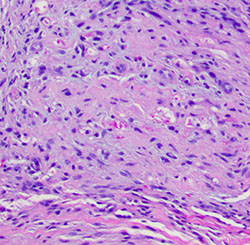

Atypical meningioma

More aggressive tumor due to presence of brain invasion (most important criteria in dx'ing), inc mits (from 4 up to 20 per 10 hpfs), prominent nucleoli (macronucleoli), sheet-like growth pattern, inc NC ratio, inc cellularity, spontaneous necrosis

- it is ok if it invades the skull, but not the brain itself

- WHO grade II

Atypical meningioma - brain invasion